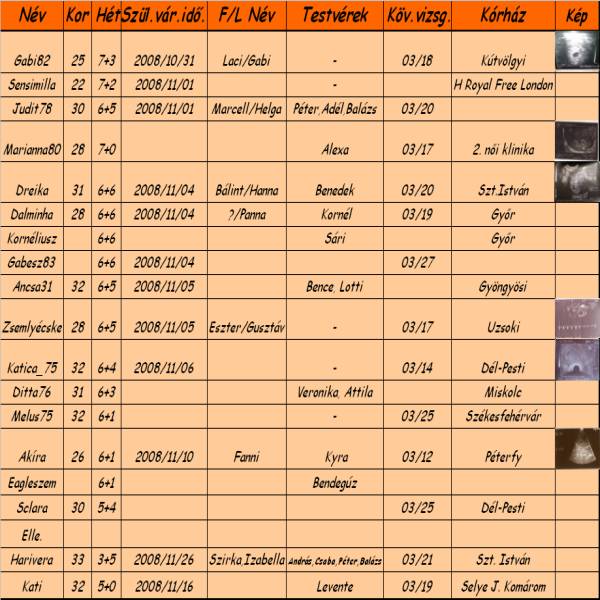

2008.03.17 10:12

2008.03.17 11:51

2008.03.17 12:54

2008.03.17 13:23

2008.03.17 13:44

2008.03.17 14:15

tesztek:)

tesztek:)

Én és Bendi [/img]

Én és Bendi [/img]2008.03.17 14:46

2008.03.17 15:19

2008.03.17 15:24

2008.03.17 15:27

2008.03.17 15:34

2008.03.17 15:36

2008.03.17 16:19

2008.03.17 16:27

2008.03.17 16:31

2008.03.17 17:53

2008.03.17 17:54

2008.03.17 19:22

2008.03.17 19:51

2008.03.17 21:54

2008.03.18 08:53

2008.03.18 11:41